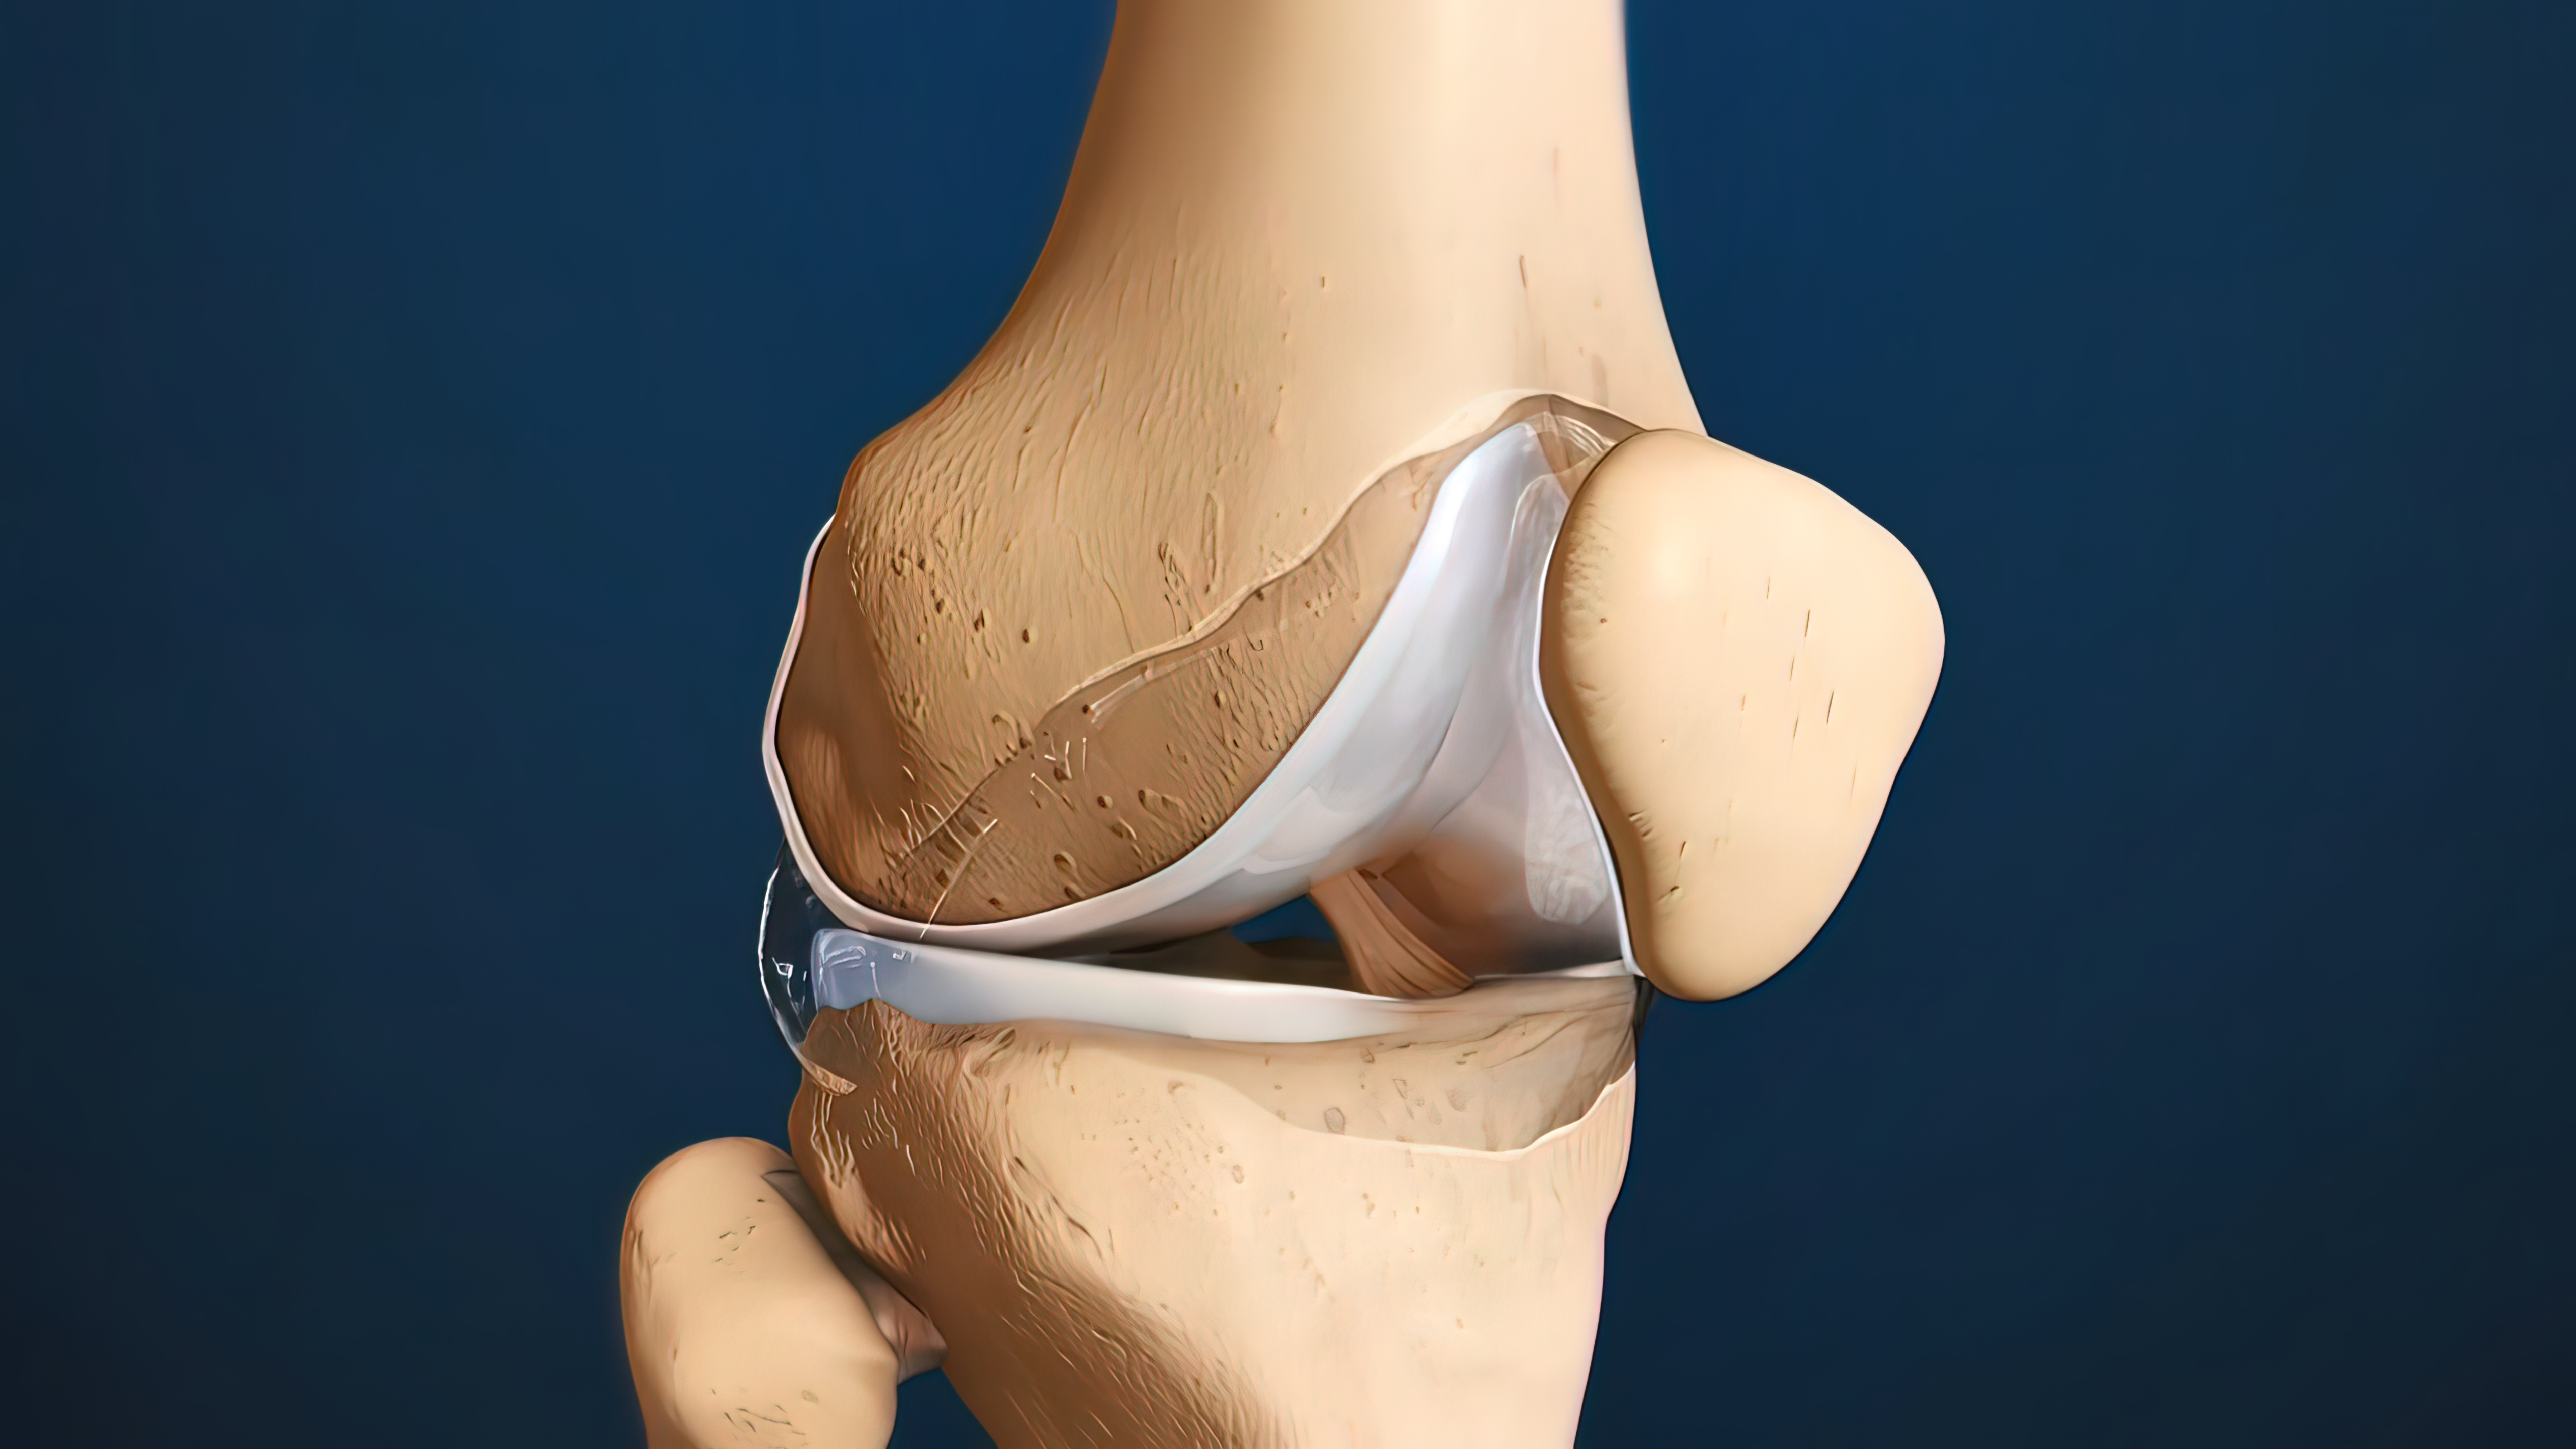

米琨:如何规范进行Oxford牛津单髁置换手术!